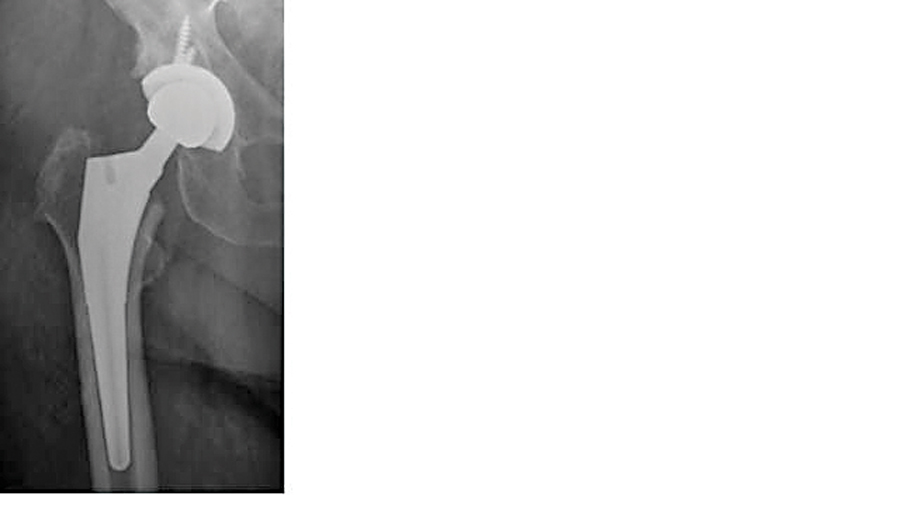

Cementless total hip arthroplasty with prophylactic femoral cable